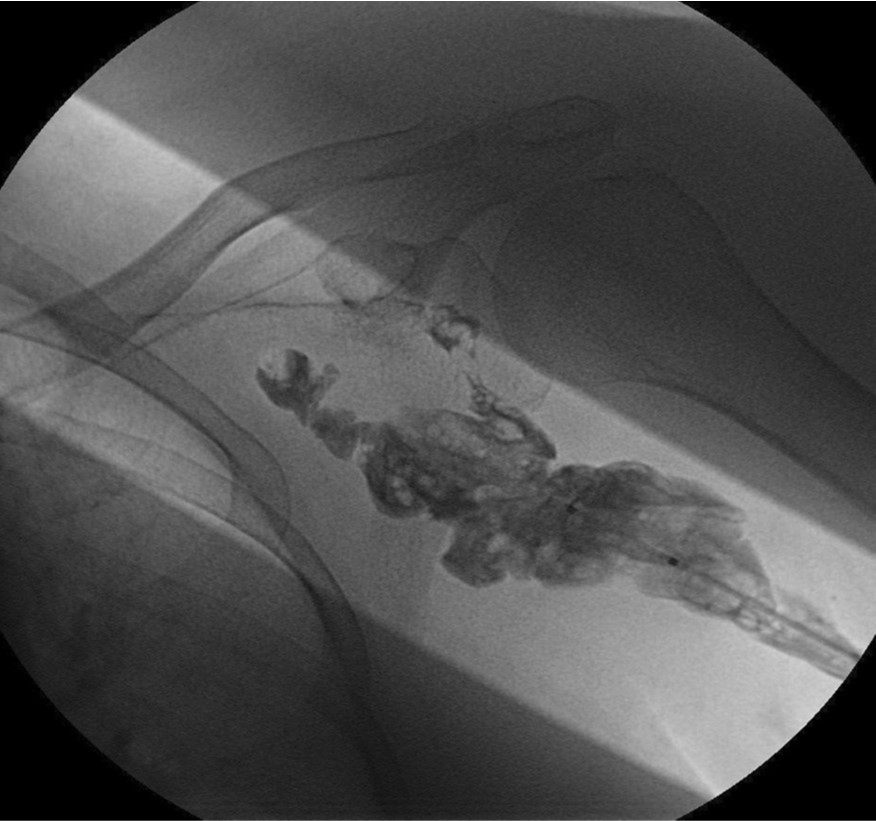

환자의 AV fistula는 초음파상 total thrombotic occlusion 된 상태였으며 시술 전 urokinase 100000 unit를 사용하여 thrombolysis and aspirated thrombectomy를 시행하였다. 그 후 시행한 shuntogram(Fig. 1) 상 left basilic vein 의 total ocdusion을 보이며 초음파상 remant vein의 크기는 1mm 이하로 확인되었다. 투시하에서 확인되는 outflow vein은 없었기에 초음파 유도하에 5 Fr Kumpe catheter(Soft-Vu, AngioDynamics, USA, NY) 에 0.035’ straight-tip guide wire(Terumo, Tokyo, Japan)를 사용하여 막힌 left basilic vein으로 15cm 이상 진행하였으며(Fig. 3), 4mm balloon (synergy, Boston, Ireland)를 사용하여 blind angioplasty를 하며 true lumen으로의 진행을 시도하였으나 실패하였다(Fig. 4). 더 이상의 antegrade로의 접근은 어려울 것으로 판단하여 regrograde approach를 위하여 left internal jugular vein 을 초음파 유도하에 9Fr sheath( Accu-Sheath, Sungwonmedical, Korea, Cheongju)을 사용하여 access 하였다. (Fig. 5A) 그리고 5Fr Cobra & sherpherd hook catheter (A&A M.D., Korea, Sungnam) 를 이용하여 left axillary vein으로의 접근을 시도하였다(Fig. 5B).

Fig. 1.

Occlusion state of left basilica van with collateral flow